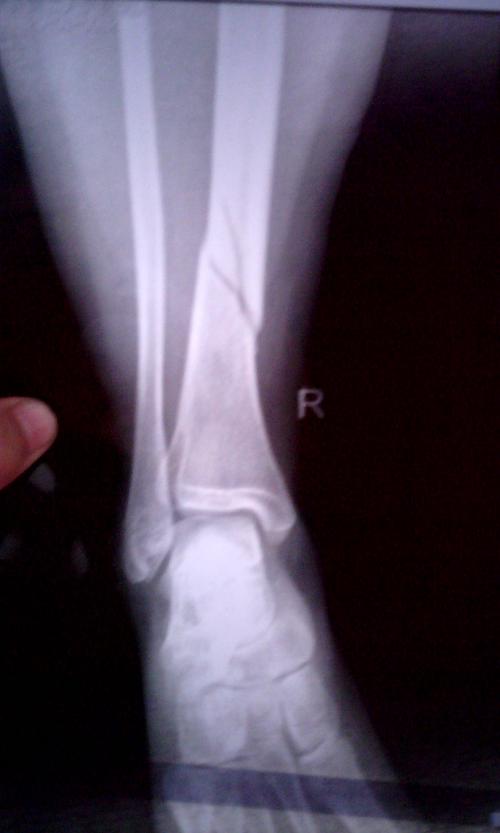

胫骨骨折打石膏

胫骨骨折打石膏,胫骨骨折打石膏图

治疗部分病例展示——腓骨下端轻微骨折石膏托外固定

型骨折,未涉及关节面或者胫骨近端干骺端,通常可以采用非手术长腿石膏

小腿胫骨下端骨折,打石膏要打多久?能完全复位吗?

先将外踝或腓骨骨折复位内固定通过前外侧纵行切口显露外踝及胫骨干

治疗方案: 1,先行胫腓骨骨折手术复位内固定治疗,术后长腿石膏膝关节

胫骨骨折打石膏图